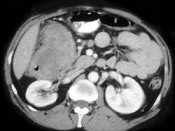

- 单项选择题男,42岁, 左下腹可触及一长条形肿块,结合图像, 最可能的诊断是 ( )

A、结肠间质瘤

B、结肠转移癌

C、结肠淋巴瘤

D、假膜性肠炎

E、结肠癌